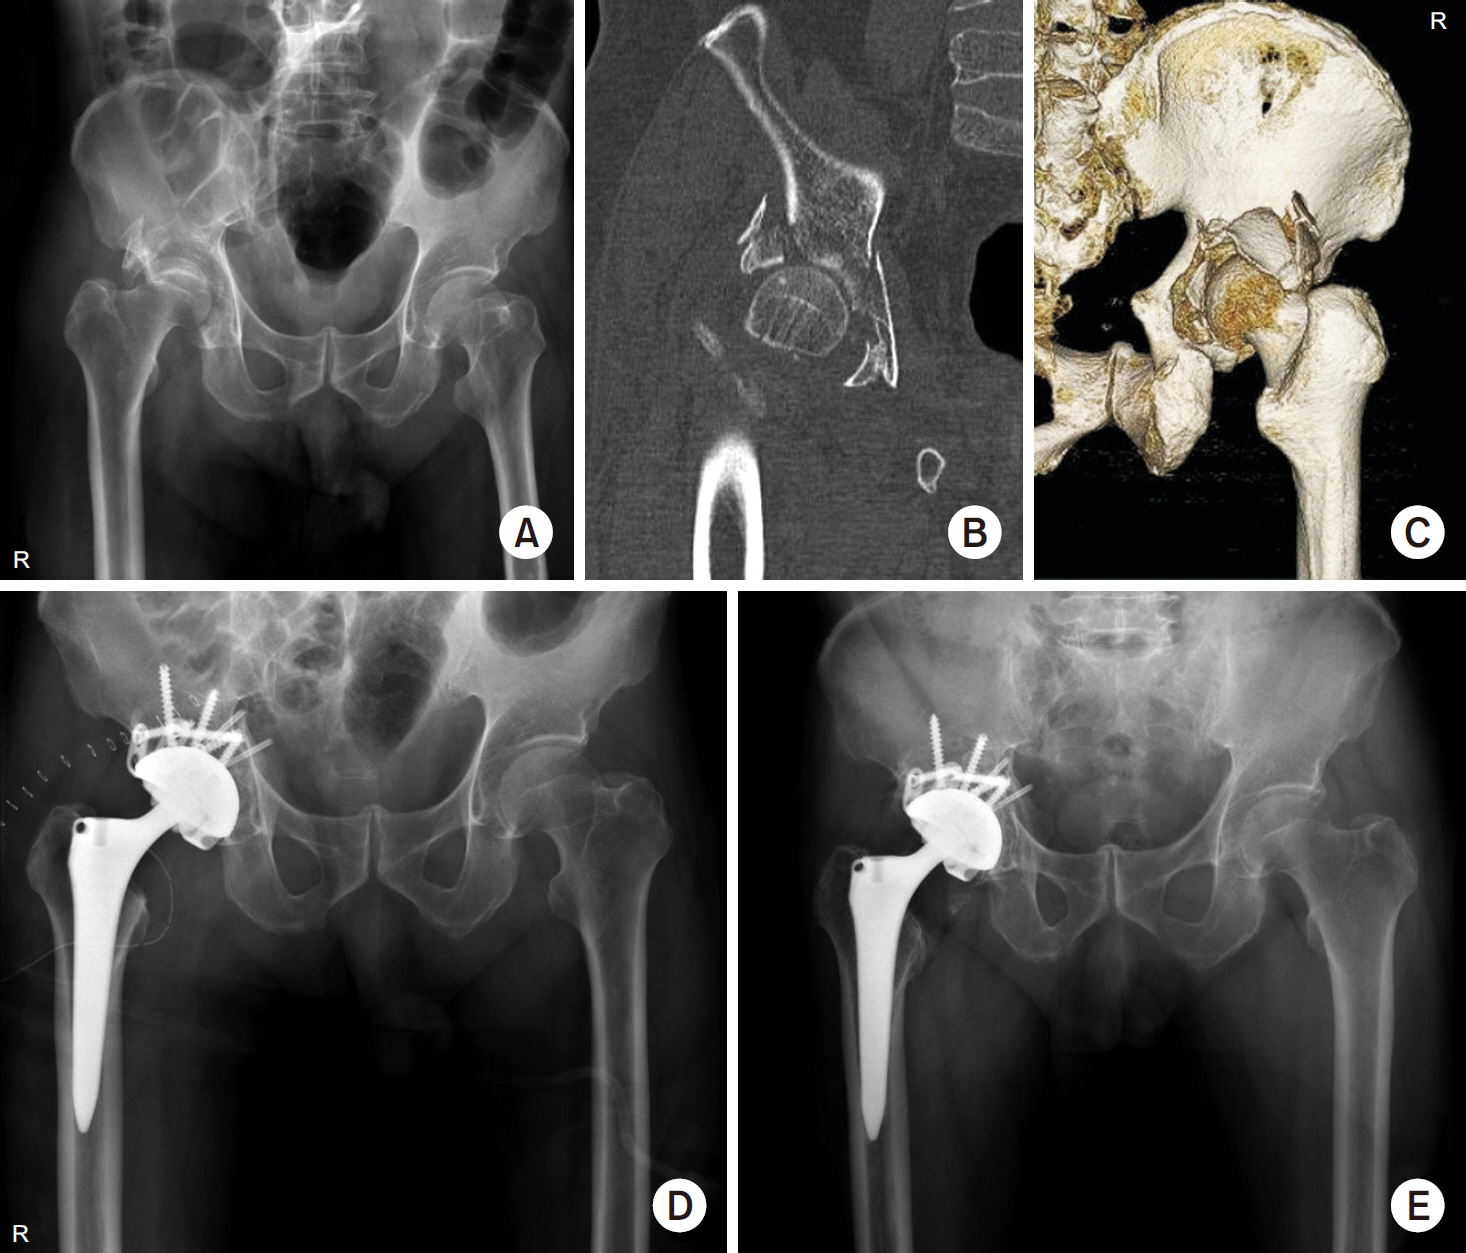

Fig. 1.

(A) Preoperative anteroposterior radiograph of a 77-year-old male showed a posterior wall fracture with osteoporosis. (B, C) Computed tomography scan showed severe comminuted fracture of the posterior wall of the acetabulum and impaction of the femoral head. (D) Postoperative anteroposterior radiograph after internal fixation with total hip arthroplasty. (E) Four-year postoperative radiograph showed stable total hip component with bone union.